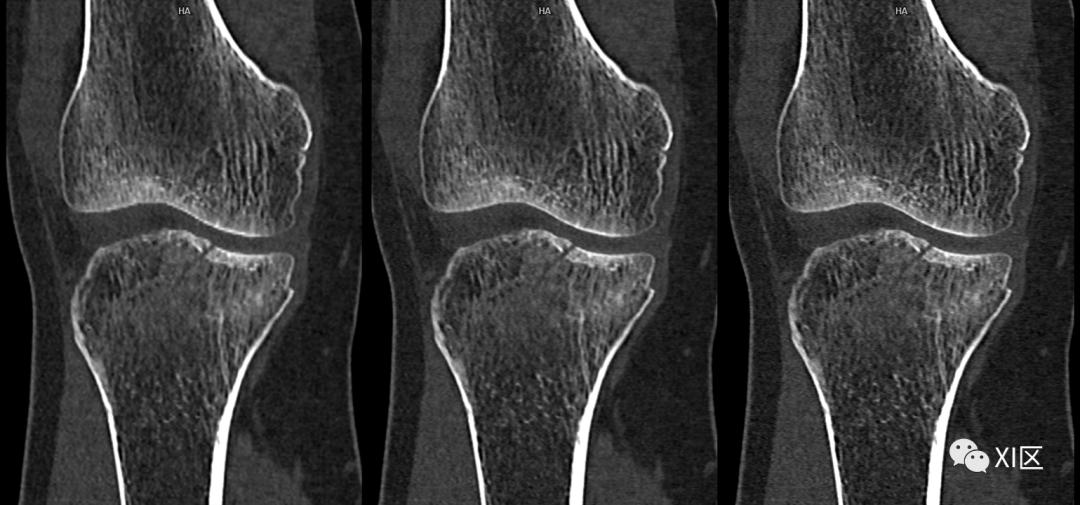

临床例案例,L2椎体骨折,清楚地显示了与64排/64层和传统模式相比,64排/128层模式空间分辨率的提高。

上图显示了不同模式的临床示例的比较。特别是与传统的CT扫描仪相比,脊柱的轮廓更清晰,可以看到更多的细节。

SOMATOM Definition Flash光子CT常规重建0.6 mm(128x0.6 mm)图像(左)与IVR重建0.6 mm(384x0.6 mm)图像(右)比较。使用IVR技术的图像关节面更平滑,骨小梁及骨折细节显示更清晰。

SOMATOM Force CT常规重建0.6 mm(192x0.6 mm)图像(左)与IVR重建0.6 mm(288x0.6 mm)图像(中)0.6 mm(576x0.6 mm)比较(上排:全局视图;下排:局部放大显示)。使用IVR技术的图像关节面更平滑,骨小梁及骨折细节显示更清晰。